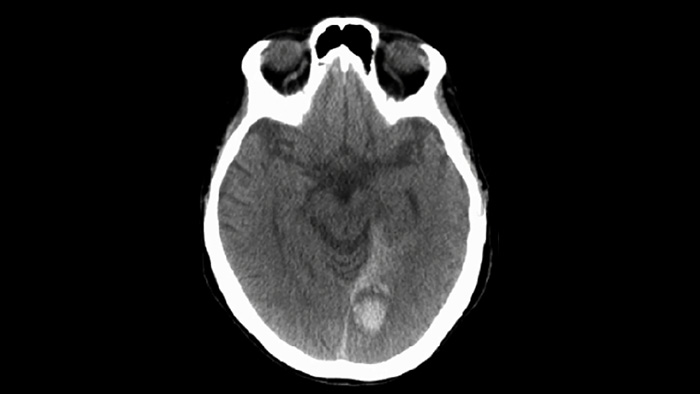

Verwenden Sie die SmartCT Soft Tissue Bildgebung der Neurovascular Suite zur Beurteilung des Behandlungserfolgs und Erkennung von Blutungen.